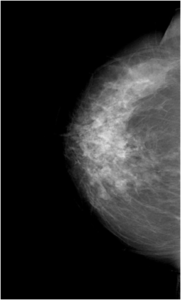

Bilateral Mammograms revealed increased reticular densities in the upper half of the right breast. A 16 mm well defined nodule seen in the left subareolar region. BIRADS 3/4 Bilateral breast ultrasound revealed extensively dilated ducts showing thickened walls and intra ductal contents corresponding to the increased reticular densities on the mammogram of right breast. Left breast revealed a 17 x 10 mm well defined low echogenic lesion with posterior enhancement in the left subareolar region. BIRADS 3 MRI showed segmental clumped / clustered ring enhancement extending from 10 to 2 O’ clock position in the right breast with extensive ductal branching and intraluminal contents extending till the nipple suspicious for DCIS. Left breast revealed a benign 16 x 14mm well defined nodule in the lower inner quadrant close to the nipple. BI-RADS-4.